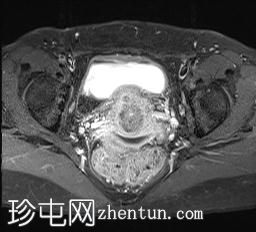

轴位

T2加权像

可见局部晚期浸润性内生型宫颈癌,肿瘤大小为30 x 32 x 48 mm。该肿瘤已侵犯宫颈前唇和后唇的深层间质,以及子宫肌层的下段。

此外,肿瘤还累及宫旁组织。影像学检查发现异常淋巴结肿大,最大短轴直径(SAD)为10 mm,位于髂总血管分叉处和髂内动脉链下方。该淋巴结肿大在弥散加权成像(DWI)上显示水限制,且增强扫描后可见强化。